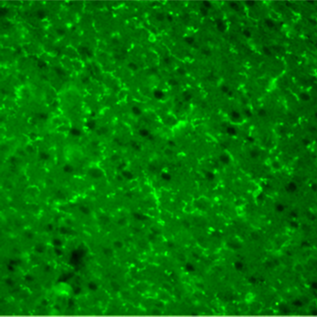

Immunohistochemistry was performed on mouse brain (frozen sections) using anti-P2RY12 and anti-Iba1 antibodies.

P2RY12

Primary Antibody: Anti P2RY12, Guinea Pig (Product Number: 011-28873, This product) 1:1,000

Secondary Antibody: Alexa Fluor® 488 AffiniPure Goat Anti-Guinea Pig IgG (H+L) (Jackson ImmunoResearch, Product Number: 106-545-003)

[Result]

The co-localization of P2RY12 and Iba1 signals was confirmed.